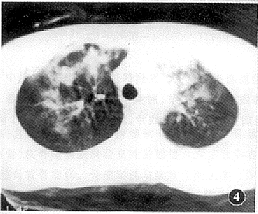

创伤性湿肺的CT表现是肺间质及肺泡的广泛挫伤和撕裂伤所引起的复合性改变。本组病例所显示的CT征象如下:(1)肺血管影增浓、模糊且粗细不均者16例(图1);(2)肺实质内散在斑点状、小片絮状稍高密度灶,边缘模糊不清者24例(图2);(3)呈磨玻璃改变的云雾状稍高密度灶,似一层薄纱复盖肺野(即“面纱征”)19例(图3);(4)大片状或呈叶、段分布的高密度灶,其内密度欠均匀,边缘不规则且模糊者20例(图4);(5)显示有大小不等、形态不规则的薄壁囊腔样低密度灶者16例(图5),囊腔内见小液平5例。上述CT表现在同一例中常混合存在。本组中CT发现有血气胸者16例,单纯血胸9例,单纯气胸6例,肋骨骨折17例,胸椎骨折3例,纵隔气肿4例,胸壁软组织积气10例,外伤性肺不张5例,肺内血肿9例。

图4 肺实质损伤渗血融合成大片状高密度灶